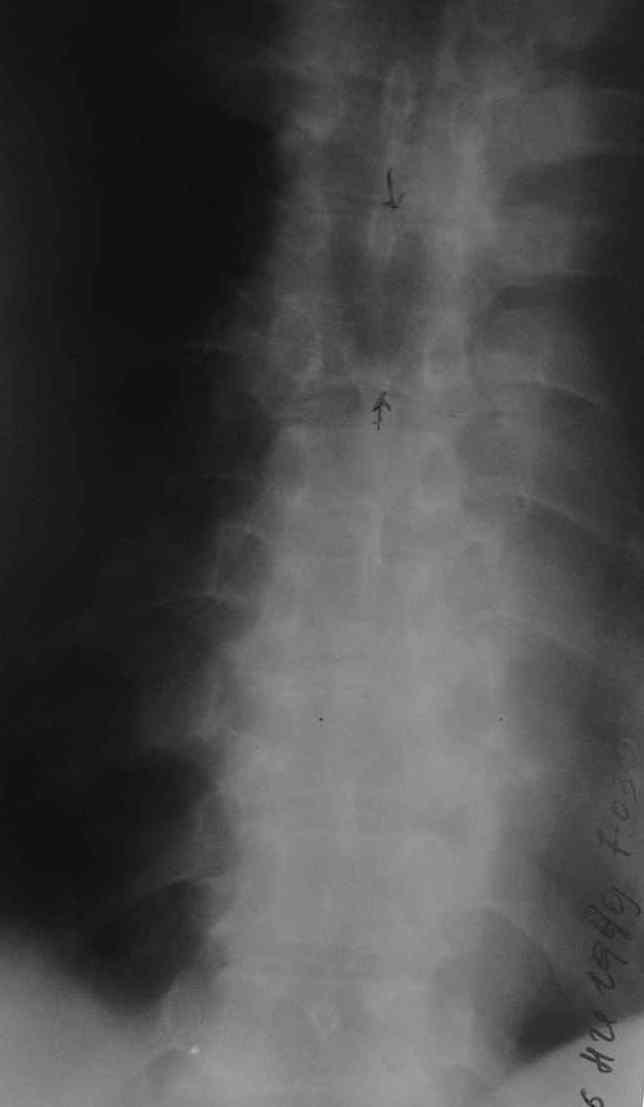

1. Rо-графия грудного и поясничного отделов позвоночника - деструкция с клиновидной деформацией Th5-6. Закл.: застарелый компрессионный перелом? Мт? 2. УЗИ внутренних органов - внутренние органы без патологии. Простата визуализируется с трудом. Края неровные, размеры 6,2х4,8х5,3 см., структура неоднородная. Объем мочевого пузыря - 600,0 мл. Заключение : Хр. б\к холецистит, Аденома простаты. Сч простаты? 3. ФГДС - заключение: Эрозивный дуоденит. Атрофический гастрит. 4. Рентгенография легких - без патологии. 5. Ретроспективный пересмотр флюорограмм за последние 3 года - без патологии. Повторно выполнены клинические и биохимические анализы крови. Заслуживает внимания только нарастание лейкоцитоза (L - 14,0П-4,С-68,Л-64,М-5, СОЭ - 65 мм.\ч). Ликвор: цвет - светло-желтый, ксантохромия- наблюдается, прозрачность - мутная, нейтрофилы - 95%, лимфоциты - 5%, цитоз - 588х106/л, белок - 9,9 промилей. В осадке - I пробирка: L- в большом количестве, Э- неизмененные, в большом количестве,Э- измененные, 1-3 в п\з. II пробирка: L - в небольшом к-ве, Э - неизмененные, 7-10 в п\з, Э- измененные, 2-3 в п\з. К ранее назначенному лечению добавлены инфузионная терапия, антибиотики ( цефтриаксон, ципринол), гормональная терапия (дексаметазон 8,0 мгх2 р\д), гепарин, диуретики, посиндромная терапия. Осмотрен урологом, онкологом. Достоверных данных за наличие Мт. не установлено. В связи с неясностью диагноза, был направлен на КТ в Тираспольскую РКБ. 21 марта больной скончался. На вскрытии - внутренние органы без признаков какой-либо патологии. При разведении волокон передней продольной связки в проекции Th4-6 была вскрыта гнойная полость с наличием деструкции тел указанных позвонков, с прорывом гнойника в позвоночный канал. Дуги и отростки позвонков - без признаков поражения. Гной сливкообразной консистенции, зеленоватого цвета. Гнойных затеков в мягких тканях также не обнаружено.Таким образом, выставлен п\а диагноз: гнойный остеомиелит тел Th4-6 c прорывом в позвоночный канал.

Насчет лечения - вполне адекватная консервативная терапия. Возможно было дополнить введение постоянного эпидурального катетера с введением антибиотиков и дренированием гноя(еще вариант - введение двух эпидуральных катетеров на разных уровнях, положение пациента на кровати с приподнятым головным концом, введение антибиотиков только в верхний. своеобразный "лаваж" позвоночного канала). Идеалом, конечно, была бы санация очага. На представленной КТ не совсем видно дату(сделана уже в период обострения?). На КТ можно заподозрить гнойную природу очага по плотности, характеру распространения. После удаления очага возможны множество вариантов выполнения дефектов.

КТ от 20 марта 2007 г. В приложении - описание КТ.

Обратите внимание, радиолог Тираспольской РКБ тоже подозревает остеомиелит. При этом, рекомендует консультацию фтизиатра.

Судя по представленным рентгенограммам и МР-томограмме (контактная деструкция тел позвонков, натечный абсцесс), анамнезу(медленное развитие заболевания) - нельзя было исключить туберкулезное поражение позвоночника. Собственно об этом забывать в таких случаях нигода нельзя. Так как тогда требуется специфическая противотуберкулезная медикаментозная подготовка.